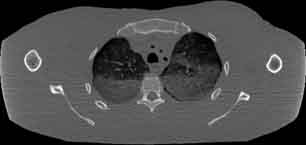

Visible Human male: Sectio transversalis 1349

CT